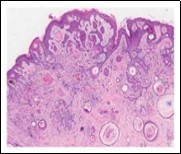

Lesions are generally superficial and infrequently invade lower dermis. Tendency for peri-neural or intra-neural infiltration, cogitated in adjunctive cutaneous carcinomas, is exceptional in desmoplastic trichoepithelioma. Nevertheless, desmoplastic trichoepithelioma can be exemplified as a component of particularly desmoplastic, cutaneous carcinomas demonstrating foci of peri-neural involvement 4, 5. Figure 1, Figure 2, Figure 3, Figure 4, Figure 5, Figure 6, Figure 7, Figure 8.

Figure 1.Desmoplastic trichoepithelioma demonstrating aggregates of basaloid cells with numerous keratinous horn cysts interspersed in an intensely fibrotic stroma 9.